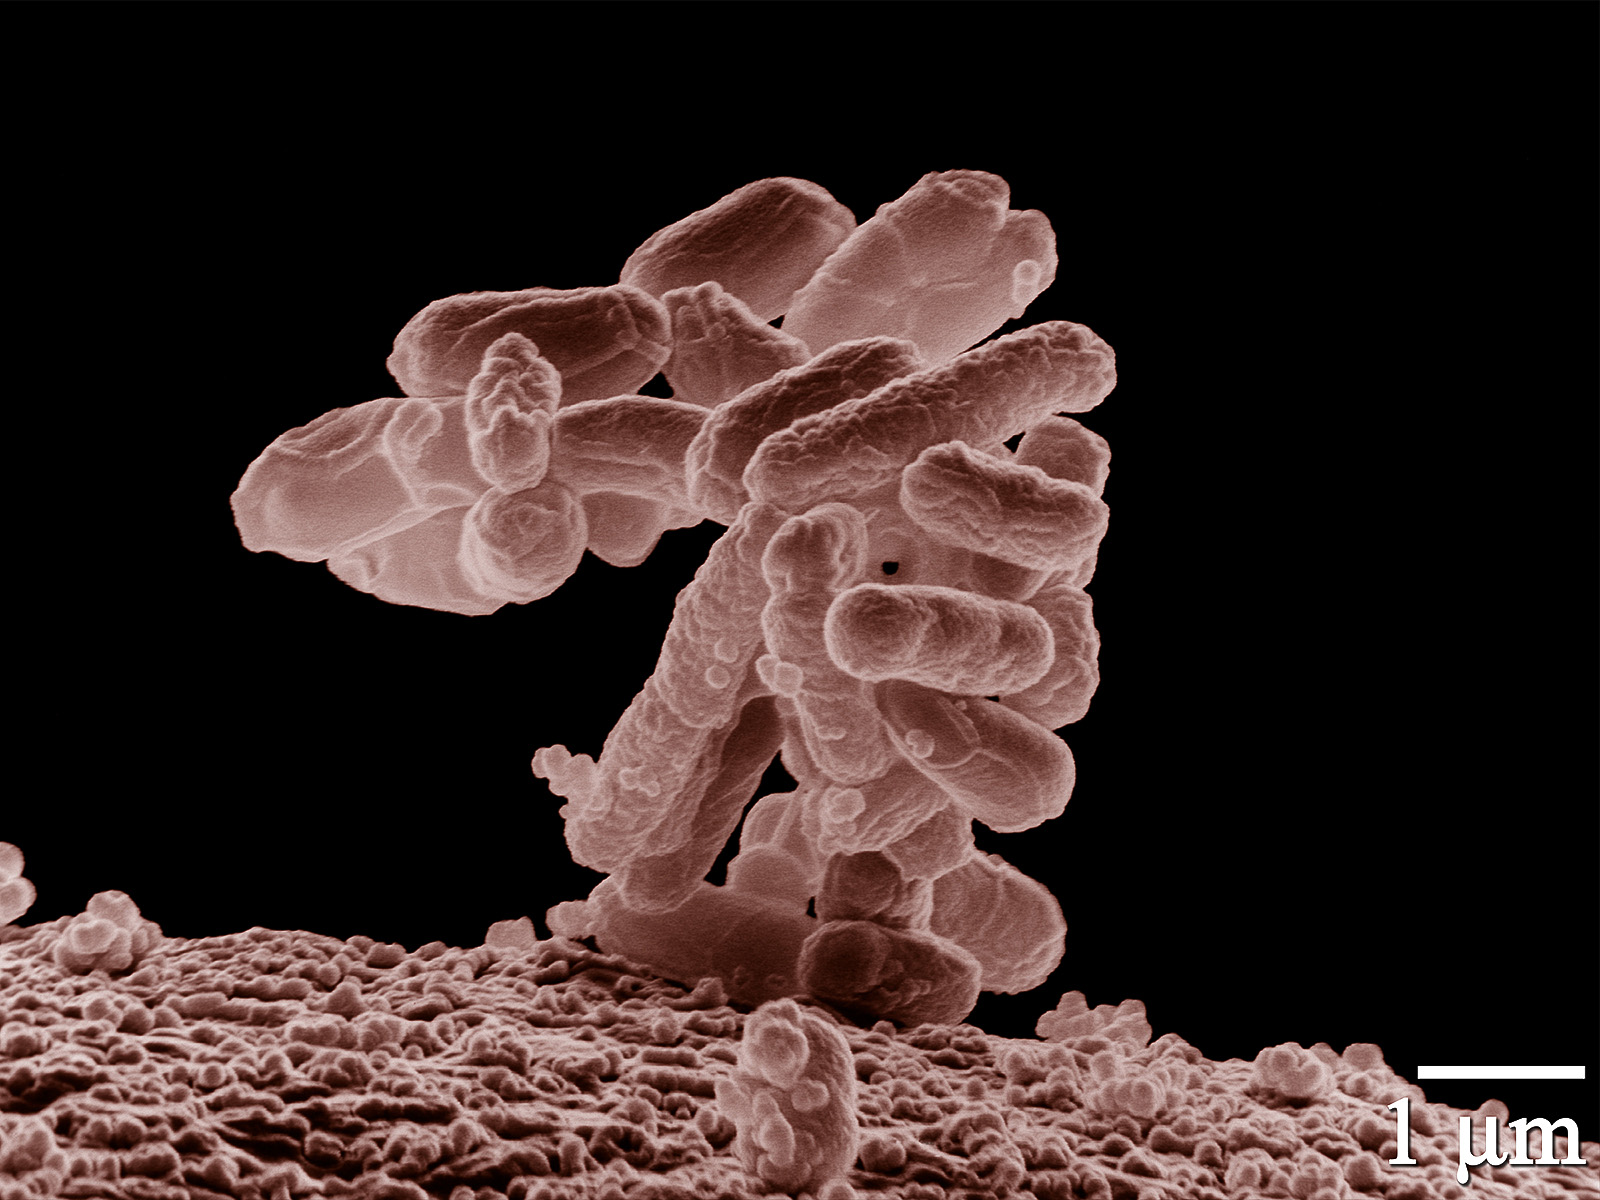

1. Presença de bactérias perigosas

Carnes cruas podem estar contaminadas com bactérias como:

-

Salmonella

-

Escherichia coli (E. coli)

-

Listeria

Esses microrganismos podem causar intoxicação alimentar, levando a sintomas como: